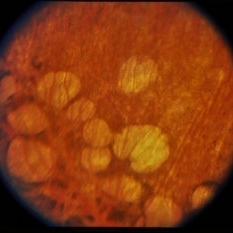

Depigmented areas and hyperpigmentation.

Condition/keywords: gyrate atrophy